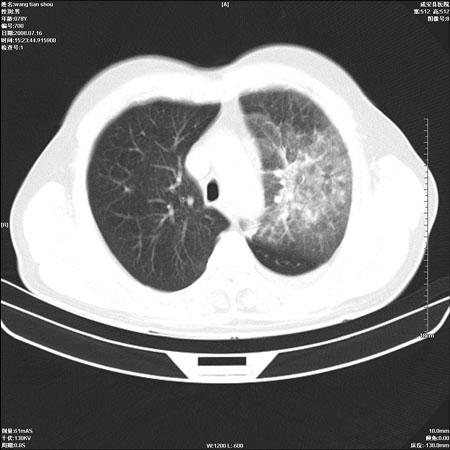

以下是引用qingjing在2008-7-16 19:55:00的发言:[br]1、左上肺不张并堵塞性炎症,建议支气管镜详查;[br]2、左侧胸腔少量积液。

以下是引用wzr在2008-7-16 20:26:00的发言:[br]左肺肺不张伴阻塞性肺炎!另:左侧胸腔少量积液。建议纤支镜检查!